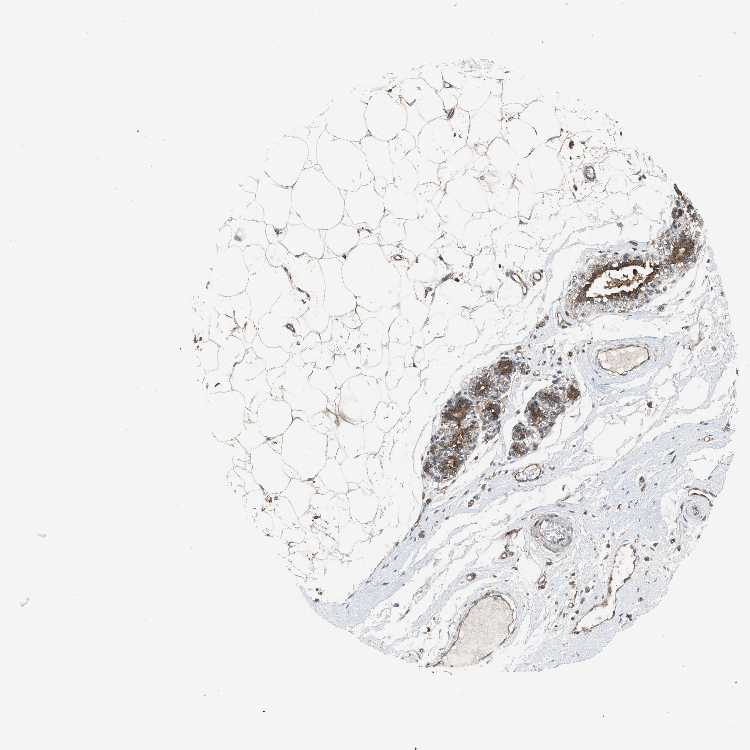

BREAST - Antibody stainingi

Antibody staining in the annotated cell types in the current human tissue is reported as not detected, low, medium, or high, based on conventional immunohistochemistry profiling in selected tissues. This score is based on the combination of the staining intensity and fraction of stained cells.

Each image is clickable and will lead to virtual microscopy that enables deeper exploration of all samples and also displays staining intensity scores, fraction scores and subcellular localization as well as patient and tissue information for each sample.

Antibody HPA021197

Adipocytes Low

Glandular cells High

Myoepithelial cells Medium